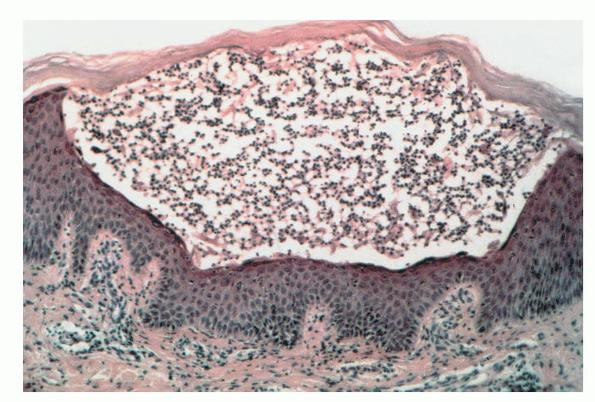

SPD may be associated with a monoclonal gammopathy, which most commonly is an IgA paraproteinemia. Some of these cases eventuate in an IgA myeloma and may have IgA squamous intercellular substance deposits. Histopathology. The pustules are subcorneal and contain neutrophils, with only an occasional eosinophil . |

The underlying slightly edematous stratum malpighii contains a small number of neutrophils. Only a few spongiform pustules are formed. In some instances, a few acantholytic cells are found in the base of the pustule, most likely because of proteolytic enzymes present in the pustular contents. They may be partially attached to the epidermis or may lie free in the pustule among the neutrophils. The dermal papillae contain dilated capillaries and a perivascular infiltrate composed of neutrophils and a few eosinophils and mononuclear cells. |